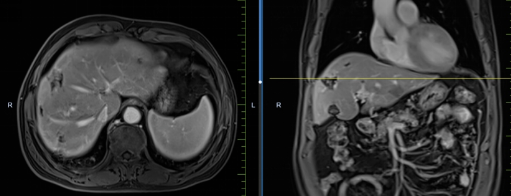

患者馬某某,男,60歲,因腹部不適行胃鏡及腹部CT,提示胃癌、多發(fā)淋巴結(jié)轉(zhuǎn)移、肝轉(zhuǎn)移,胃部病灶大小約11*6cm,淋巴結(jié)最大病灶約6*3cm,肝臟病灶最大約8.8*7cm。經(jīng)6周期化療+免疫,聯(lián)合中醫(yī)中藥后,病灶明顯縮小,進(jìn)入維持治療階段,身體狀況與常人無(wú)異。

治療前